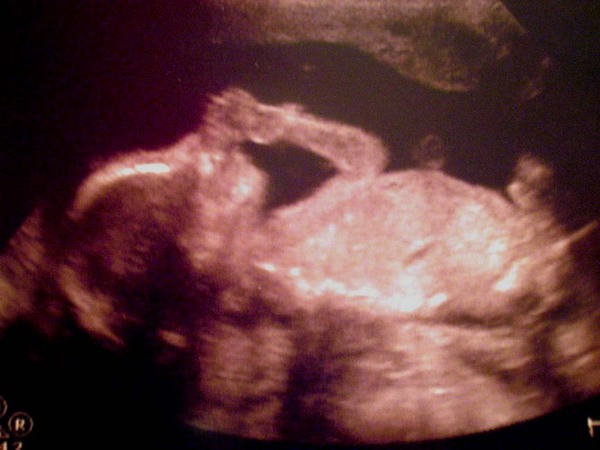

總之我也終於等到了期待以久

第二次也是最後一次的二十週超音波了

小小人真的給他安穩的橫躺在肚子裡

什麼腎臟膀胱脊椎都不好檢查

任憑我如何翻東翻西,就是不動如山

結果臭臉小姐只好請我下床

出去走個二十分鐘再回來

這回小小人兒可配合多了

該看的都給看

不該給看的也給看

所以我親愛的小小人兒

可是個正港的男子漢

總之除了謎底揭曉以外

很放心地知道一切都好

所有的成長除了正常還都超標!

頭大,肚子大,手長腳長